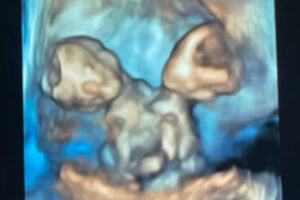

Gebeliğin yedinci haftasında yapılan denetimde, ultrasonda sırf bir kalp atışı duyulmasına karşın ikiz gebelik kuşkusu ortaya çıktı.

Anne adayı, birebir kalbi, karaciğeri, bağırsakları, diyaframı ve göbek kordonunu paylaşan ikiz kız bebeklere gebeydi.

Nicole, 32. haftada sezaryenle ikizlerini dünyaya getirdi. Maria Therese ve Rachel Clare isimleri verilen bebekler, doğum anında farklı yansılar verdi.